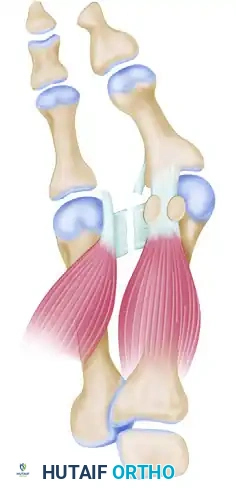

Phase 2: Medial Eminence Excision and Capsulorrhaphy

The second incision is a midline-medial approach over the first MTP joint to address the medial eminence and perform a medial capsulorrhaphy.

- Capsulotomy: Make a vertical incision in the capsule 2 to 3 mm proximal to the base of the proximal phalanx. Extend this from just medial to the extensor hallucis longus tendon, moving plantarward through the thickened abductor hallucis tendon-capsule junction, ending 2 mm medial to the tibial sesamoid. Make the inferior portion of this cut from plantar to dorsal to avoid the digital nerve.

- Wedge Excision: Depending on the redundancy of the stretched medial capsule, remove an elliptical wedge measuring 4 to 8 mm at its widest point. Taper this incision dorsally and plantarward into a V-shape.

- Exposure of the Eminence: Extend the capsular incision proximally from the dorsal edge of the vertical limb, creating an inverted "L" shape. End this 2 to 3 mm proximal to the junction of the medial eminence and the metatarsal shaft. Raise this flap (dorsal-distal to plantar-proximal) to expose the exostosis.

- Exostectomy: Resect the medial eminence using an oscillating saw. The cut must be strictly parallel to the medial shaft of the first metatarsal, beginning 1 to 2 mm medial to the sagittal groove to preserve the tibial sesamoid articulation.